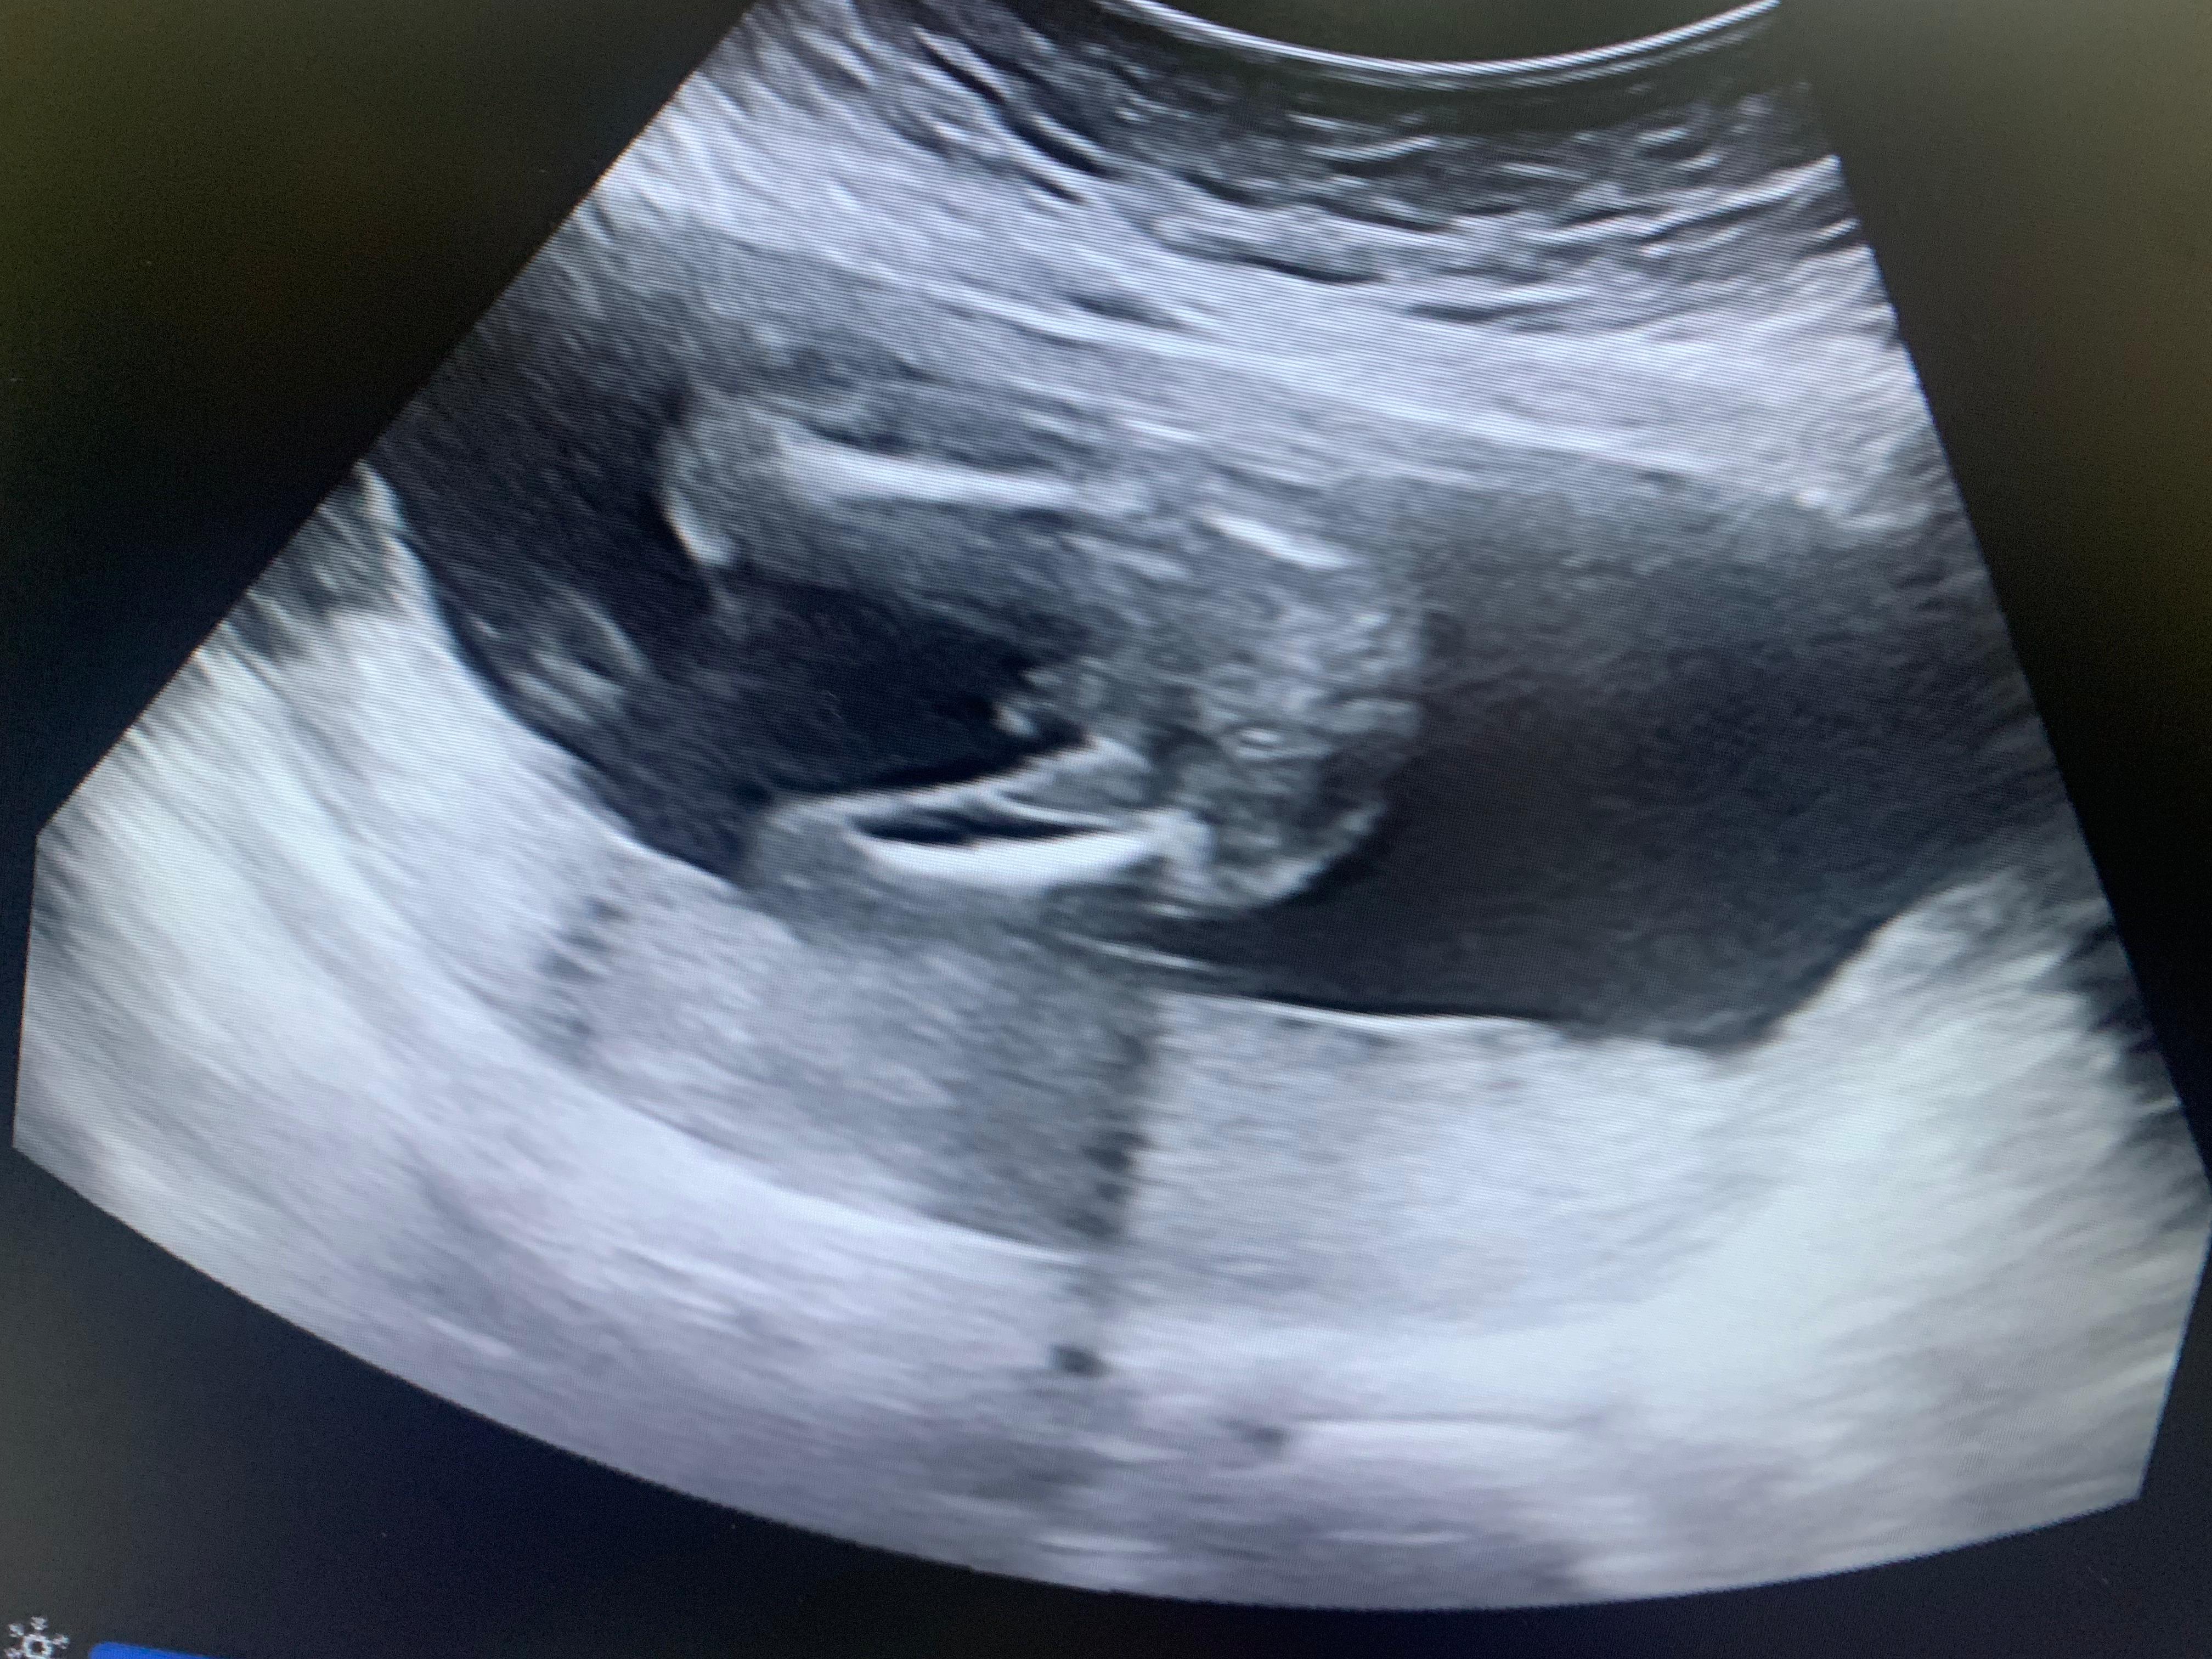

هذه الصوره الجنس ذكر ام انثى

أرغب ب معرفة نوع الجنين ايه ؟

هذا ذكر والله أعلم... 0 2026-04-01T20:29:46+00:00 2026-04-01T20:29:46+00:00